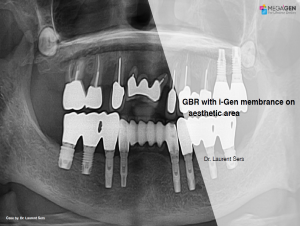

GBR with i-Gen membrance on aesthetic area

Dr. Laurent Sers,Bone regeneration,Aesthetic zone,Maxillary Anterior,#11,#21,GBR,i-Gen,MEGA ISQ,Clinical case

English

2019-10-01

PDF

1.87 Mb

Clinical cases

466